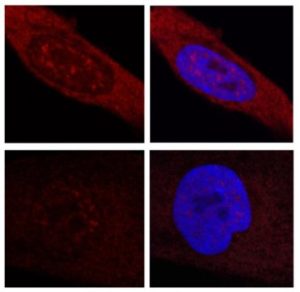

Nuove prove: come la cisteina combatte la malattia di Huntington

I ricercatori della Johns Hopkins Medicine hanno identificato una via biochimica che collega lo stress ossidativo e la cisteina nella…